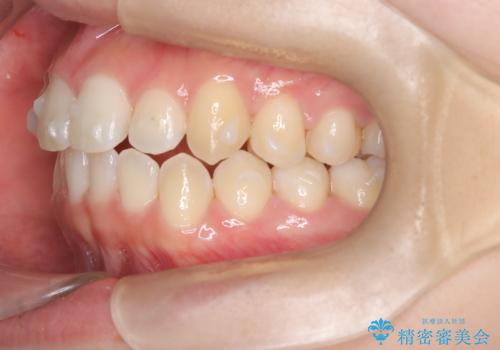

- 右上の前歯(2番)が下の歯より内側に入っている反対咬合を主訴にご来院されました。精密な検査の結果、この反対咬合を解消するためには、右上の歯列に前歯を出すためのスペースを確保する必要があると判明しました。患者様のご希望に合わせ、透明で目立たないインビザライン(マウスピース矯正)による治療計画を立案。奥歯全体を奥へ動かす遠心移動でスペースを作り、反対咬合を解消することを目指します。

今回の矯正治療では、透明なマウスピース型の装置インビザラインを使用しました。治療は、緻密なデジタル計画に基づき、奥歯から順に歯列全体を後方へ移動させる遠心移動を実施し、前歯を前に出すためのスペースを確保しました。このスペースを利用して、内側に入り込んでいた右上2番をスムーズに前方に誘導し、正常な咬み合わせへと改善。目立たないインビザラインで、機能的な咬み合わせと美しい前歯の並びを獲得していただけました。